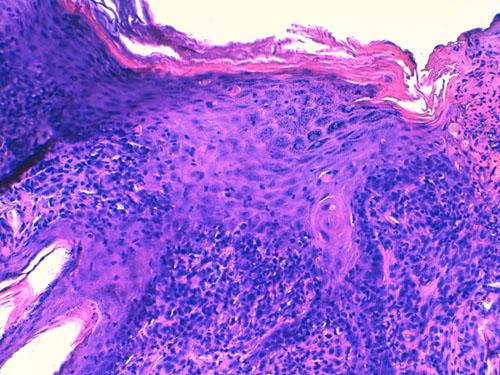

Des biopsies cutanées sont réalisées, et aucune autre antibiothérapie complémentaire n’est débutée dans l’attente des résultats. L’examen histopathologique révèle, des corps apoptotiques (kératinocytes nécrosés) sont observés au sein des couches épidermiques et dans la gaine folliculaire externe pilaire (photos 4 et 5). Des images de satellitose lymphocytaire sont présentes autour d’eux ainsi qu’une vacuolisation hydropique sous-épidermique multifocale (Photo 6). Par ailleurs, il est observé une dermatite d’interface lichénoïde marquée avec lymphocytes, de plus rares plasmocytes, des cellules présentatrices d’antigènes et des mélanophages (discrète incontinence pigmentaire) (Photo 7). Cet infiltrat lichénoïde forme également des manchons péri-annexiels. Le cycle pilaire est normal, et aucun élément figuré parasitaire ou fongique n’est noté.

cas-de-toxidermie-chez-bichon5Photo 4 et 5 : (HE*400, vue rapprochée) : 3 corps apoptotiques (kératinocytes nécrosés)

au sein des couches épidermiques, image de satellitose, infiltrat lichénoïde marqué